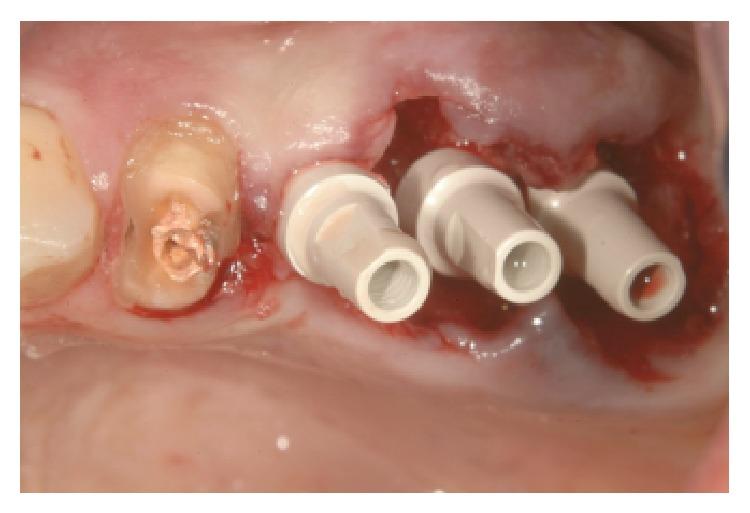

The extraction of teeth results in rapid bone resorption both vertically and horizontally in the first month. The loss of alveolar ridge reduces the chance of implant rehabilitation. Atraumatic extraction, implant placement in extraction socket, and an immediate prosthesis have been proposed as alternative therapies to maintain the volume and contours tissue and reduce time and cost of treatment. The immediate load of implants is a universally practiced procedure; nevertheless a successful procedure requires expertise in both the clinical and the reconstructive stages using a solid implant system. Excellent primary stability and high bone-implant contact are only minimal requirements for any type of implant procedure. In this paper we present a case report using a new type of implants. The new type of implants, due to its sophisticated control system of production, provides to the implantologist a safe and reliable implant, with a macromorphology designed to ensure a close contact with the surrounding bone.